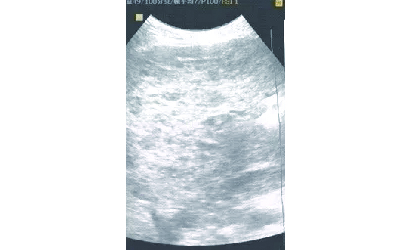

最近诊室来了一位肝血管瘤的患者,说几年前被检查出患有肝血管瘤,医生当时明明说不用采取治疗,但是这一阵子感觉不舒服,再一检查又说瘤体增大,要尽快治疗。不知道该怎么办。